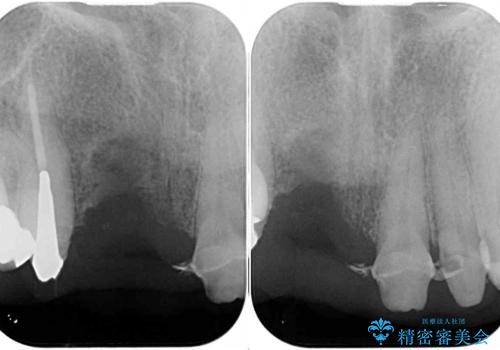

- 前歯のブリッジ治療中に装着していた仮歯が、あまりにも不自然で気になるとのことで来院された患者様です。

早急に仮歯をきれいなものに付け替え、オールセラミックブリッジにより補綴することとしました。